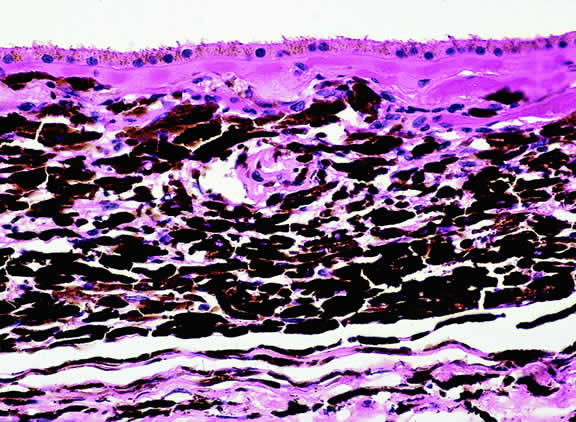

Fig. 5. Ciliary body melanocytoma. Ciliary epithelium covers intensely pigmented tumor. Melanin pigment obscures nuclei. (Hematoxylin-eosin, × 50.)

Histopathologically, melanocytomas are composed of cells that have abundant quantities of maximally pigmented cytoplasm that often obscures nuclear details, making microscopic assessment impossible11 (see Fig. 5). Bleached sections, which are a requisite for examination, show that the cells have bland nuclei and a low nuclear-to-cytoplasmic ratio (Fig. 6). Nucleoli usually are inconspicuous, but there are exceptions to the rule. Electron microscopic studies also have revealed a second population of spindle cells.15,24 Melanocytoma cells resemble the benign melanocytes found in the uvea of patients with ocular melanocytosis.